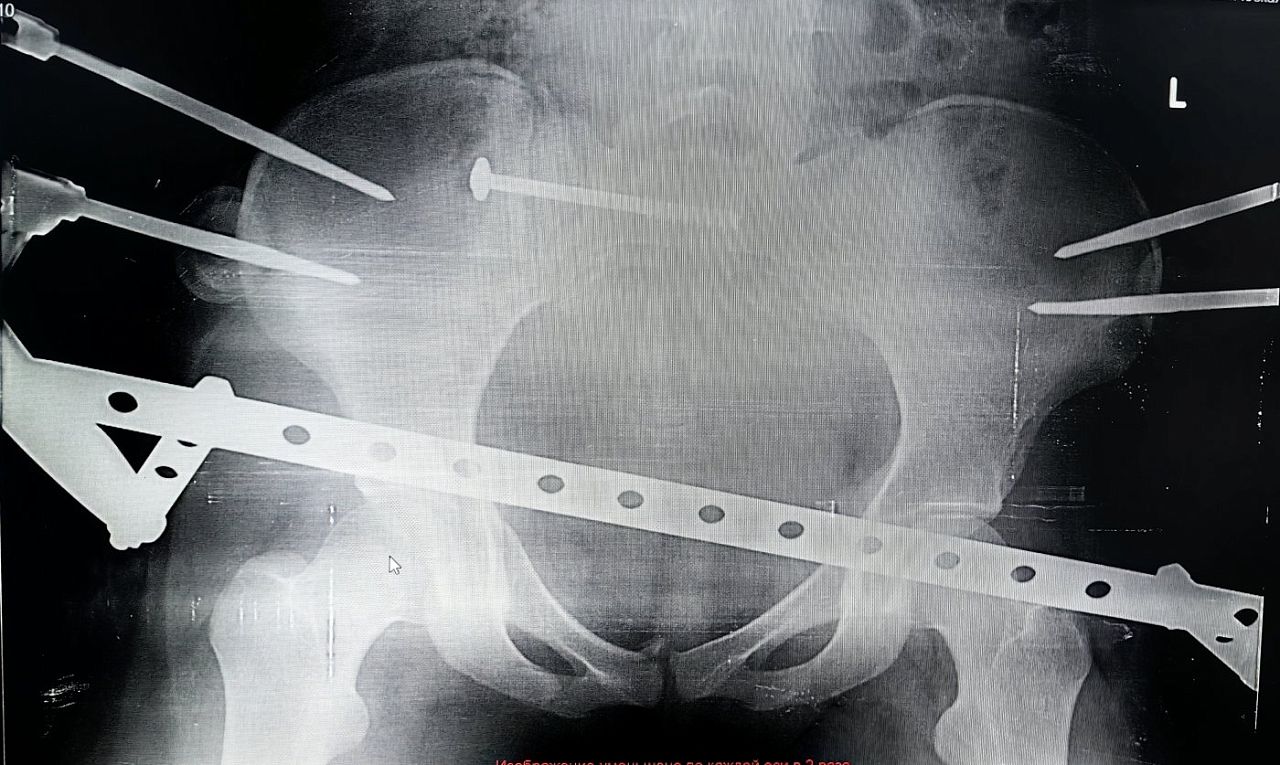

— Хотя по возрастной классификации 17-летние ещё считаются подростками, многие подходы детской травматологии и ортопедии в таком пограничном возрасте уже не эффективны. Поэтому решение приходится искать среди вариантов, применимых ко взрослому населению. В данном случае мы остановились на сложной и довольно редкой операции — малоинвазивном комбинированном остеосинтезе таза. Нам удалось с помощью внешней конструкции и имплантируемых элементов зафиксировать повреждённые крестцовую, лонную и седалищную кости. И при этом обойтись без травматичного доступа. То есть, вся операция была выполнена без разрезов, — объяснил заведующий отделением травматологии и ортопедии №1 Сергей Глиняный.

По словам медиков, существовали риски при установке илеосакрального блокирующего винта в области крестца, где проходят нервы, спинной мозг и множество сосудов. Критически важно не задеть эти структуры, поэтому операция требует от врача соответствующего опыта и высокого уровня мастерства.